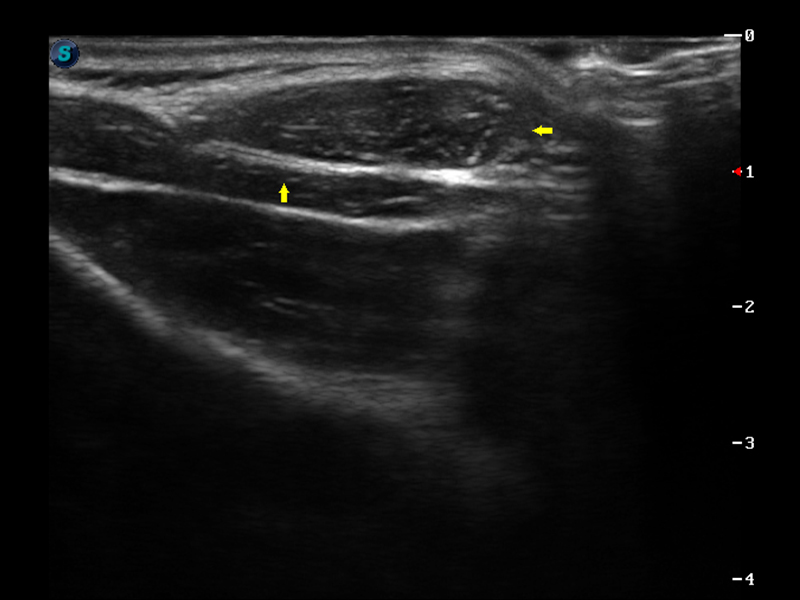

S9便携式彩色多普勒超声诊断仪是银河集团官网研发的高端便携彩超设备,外观设计新颖、产品性能卓越。S9在便携超声领域采用了突破传统的触摸屏交互设计,并以先进的软件硬件技术和设计理念,为您带来清晰的图像质量、稳定的工作性能和便捷的操作体验。